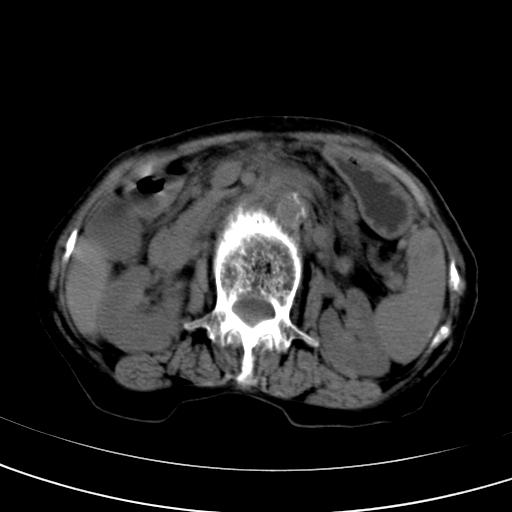

以下是引用wolft在2008-3-5 12:30:00的发言:[br]肝脏未见明显肿块影,但肝左叶增大,跨越腹中线到达脾胃前,且有一血管过去,考虑为先天变异:獭尾肝,胆囊为慢性胆囊炎急发,但胰腺头颈部有增大,密度不均匀,应该ct增强一下。

以下是引用zjzjr在2008-3-5 16:41:00的发言:[br]1.考虑慢性胰腺炎急性发作,建议增强除外占位性病变.[br]2.胆囊结石伴胆囊炎.[br]3.肝内胆管结石.